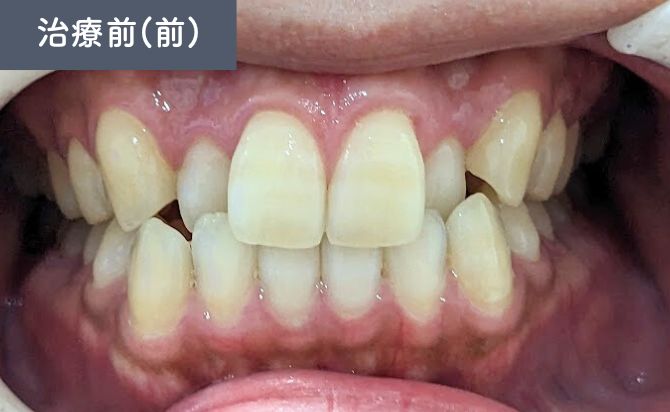

歯並びの変化(正面)

上顎1番の前方位が確認され、口元の突出感に影響していました。また、上顎2番の舌側傾斜があり、歯列全体の並びにも不均衡がみられました。

咬合状態では、右側3番が切端咬合となっており、犬歯の誘導機能に影響を及ぼす可能性がある状態でした。

さらに、下顎歯列弓が方形型であることから、上下のアーチ形態のバランスが整っておらず、前歯部の噛み合わせにも改善の余地があると判断しました。

治療終了時には、患者様が気にされていた上顎1番の突出が軽減され、前歯の位置が適正化しました。上顎2番の舌側傾斜も改善され、左右のバランスが整った歯列アーチが得られています。

右側3番の切端咬合も改善し、犬歯誘導が適切に働く咬合状態となりました。上下のアーチ形態のバランスも改善し、見た目だけでなく、機能的にも安定した咬合が確立されています。